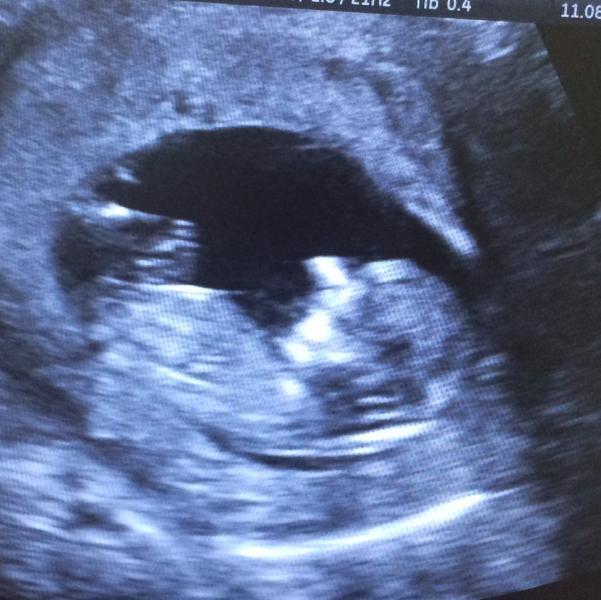

Наше фото со скрининга 😍 Такое ощущение, что малыш такоооой большой 🙈

@lizochka1444, на скрининге 13, сейчас 15:)